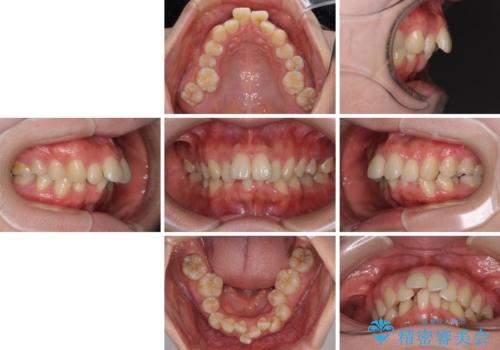

全顎的なデコボコと口元の突出感 ワイヤー装置での抜歯矯正で整った口元に

- 奥歯も含めて全体的なデコボコと前歯の突出感を気にして来院された患者様です。

上下左右第一小臼歯4本を抜歯し、ワイヤー装置にて矯正治療を行うこととしました。